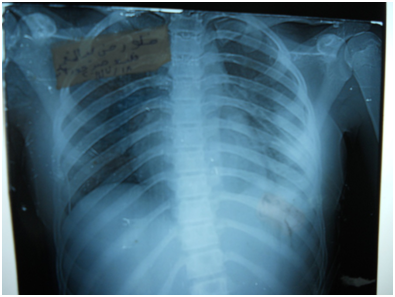

A 17-year-old girl (170cm, 60kg) presented to the emergency department with dyspnea and chest pain after a penetrating stab wound to the chest in the left sixth intercostal space mid-clavicular line, which happened 2hours earlier. Upon physical examination, Pulse was 96 beats per minute and blood pressure was 110/70mmHg, diminished air entry was noticed on the left side of chest. Chest x-ray revealed left hydropneumothorax. Tube thoracostomy was performed left intercostals tube was inserted for drainage. Post-insertion chest x-ray revealed no improvement in the picture of air fluid level (Figure 1) (Figure 2) which was further evaluated by CT that showed fluid collection posteriorly and air anteriorly (Figure 3) (Figure 4). Two days later patient had fever with vomiting and leucocytosis. The nature of the drain from the intercostal tube becomes serosangenous and less hemorrhagic with change in color associated with food. Methylene blue dye (1% concentration) taken orally by the patient was detected in the drain of the intercostal tube two minutes after ingestion (Figure 5). Oral contrast chest x-ray was done, two shots were taken one on swallowing gastrographin, it showed the esophagus outlined without any leakage (Figure 6A). The other shot taken two minutes after oral administration of gastrographin in trendlenberg position, the contrast outlined a track passing from the fundus of the stomach to the left pleural cavity and to the intercostals tube (Figures 6B) (Figure 6C). Laparotomy was performed via midline incision and findings were confirmed. It showed a 3cm orifice of the left copula of the diaphragm with a tear in the gastric fundus which was closed in two layers and the diaphragmatic tear was closed directly with continuous sutures. Two weeks later patient complicated by left empyema with thickened pleura. Thoracotomy was done for complete evacuation of pus and decortication. The patient fully recovered and was discharged 8days after thoracotomy.

Figure 2 Second day post intercostals tube insertion chest X-ray.